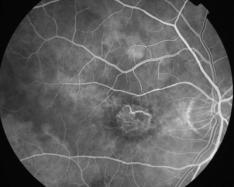

ATROPHIE AREOLAIRE CENTRALE

IMG0001.JPG